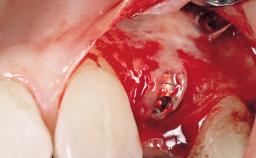

Early Placement of an Implant in a Maxillary Right Central Incisor Site

This 41-year-old female patient was referred to the clinic for the replacement of the right central incisor, since the tooth had developed a root fracture in the long axis that made extraction necessary. The healthy, non-smoking patient was first seen with the tooth still in place. A detailed Esthetic Risk Assessment was performed.The patient was worried about her dental esthetics and had high expectations for a successful treatment outcome from an esthetic point of view. The patient had a medium lip line that displayed parts of the gingiva in the anterior maxilla upon smile.

| Bone Augmentation | Horizontal|Simultaneous |

| Augmentation Materials | Autogenous chips|Xenogenous|Membrane |